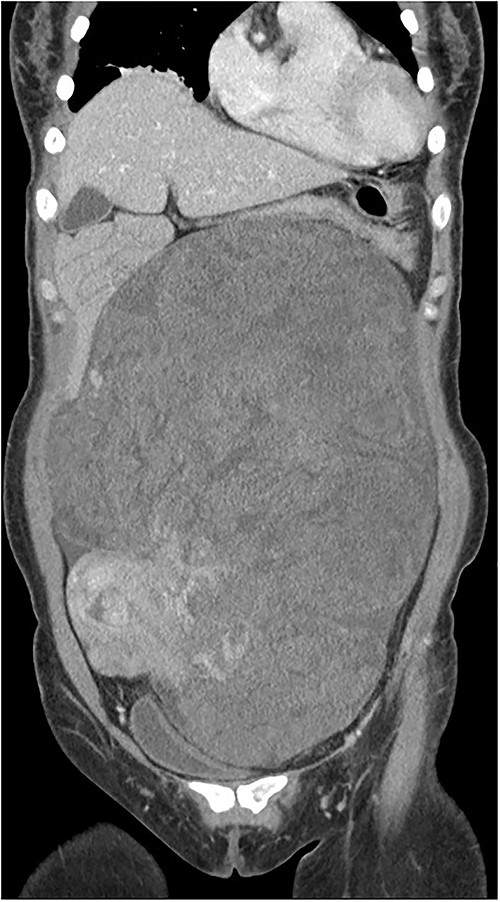

The tumor was wrapped in a grayish-white capsule in a lobulated pattern, accompanied by bleeding; necrosis was not apparent. Yellow dot-like cellular components were observed. The findings for the spindle cell neoplasm (46.5 × 25.0 × 8.0 cm) were a smooth-muscle tumor of uncertain malignant potential (stump), with necrosis absent, a mitotic count <4/10 HPF, and moderate-to-severe and focal nuclear atypia (Fig. 3). Based on these results, the diagnosis revealed that the tumor originated from smooth muscle cells and was classified as a spindle cell tumor. Immunohistological analysis showed negative results for CD34, c-kit, PAN-CK, EMA, and S-100 and positive results for Desmin and SMA. The Ki-67 index was 5% (Fig. 4).

Immunohistological analysis showed negative results for CD34, c-kit, PAN-CK, EMA, and S-100 and positive results for Desmin and SMA. The Ki-67 index was 5%.